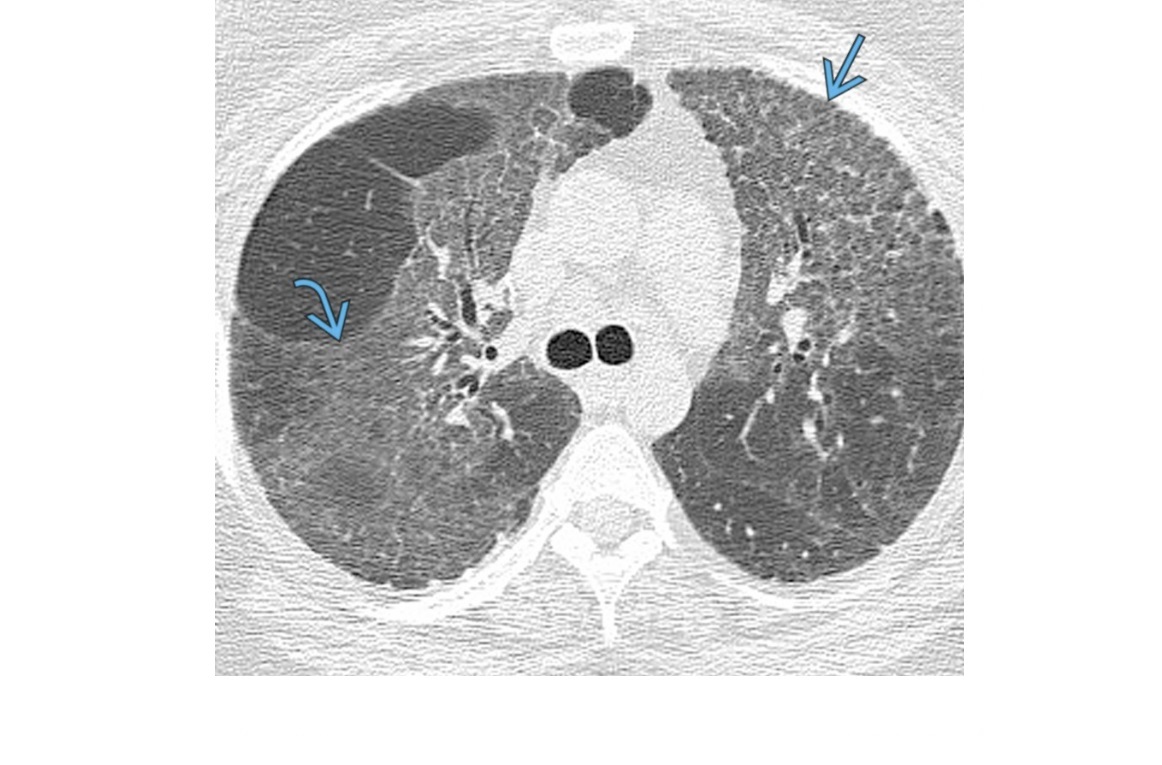

MAC

Tree in bud - terminal bronchiole filled with radiopaque material

cylindric bronchiectasis

clasically right middle lobe or lingula (aka lady windermere syndrome)